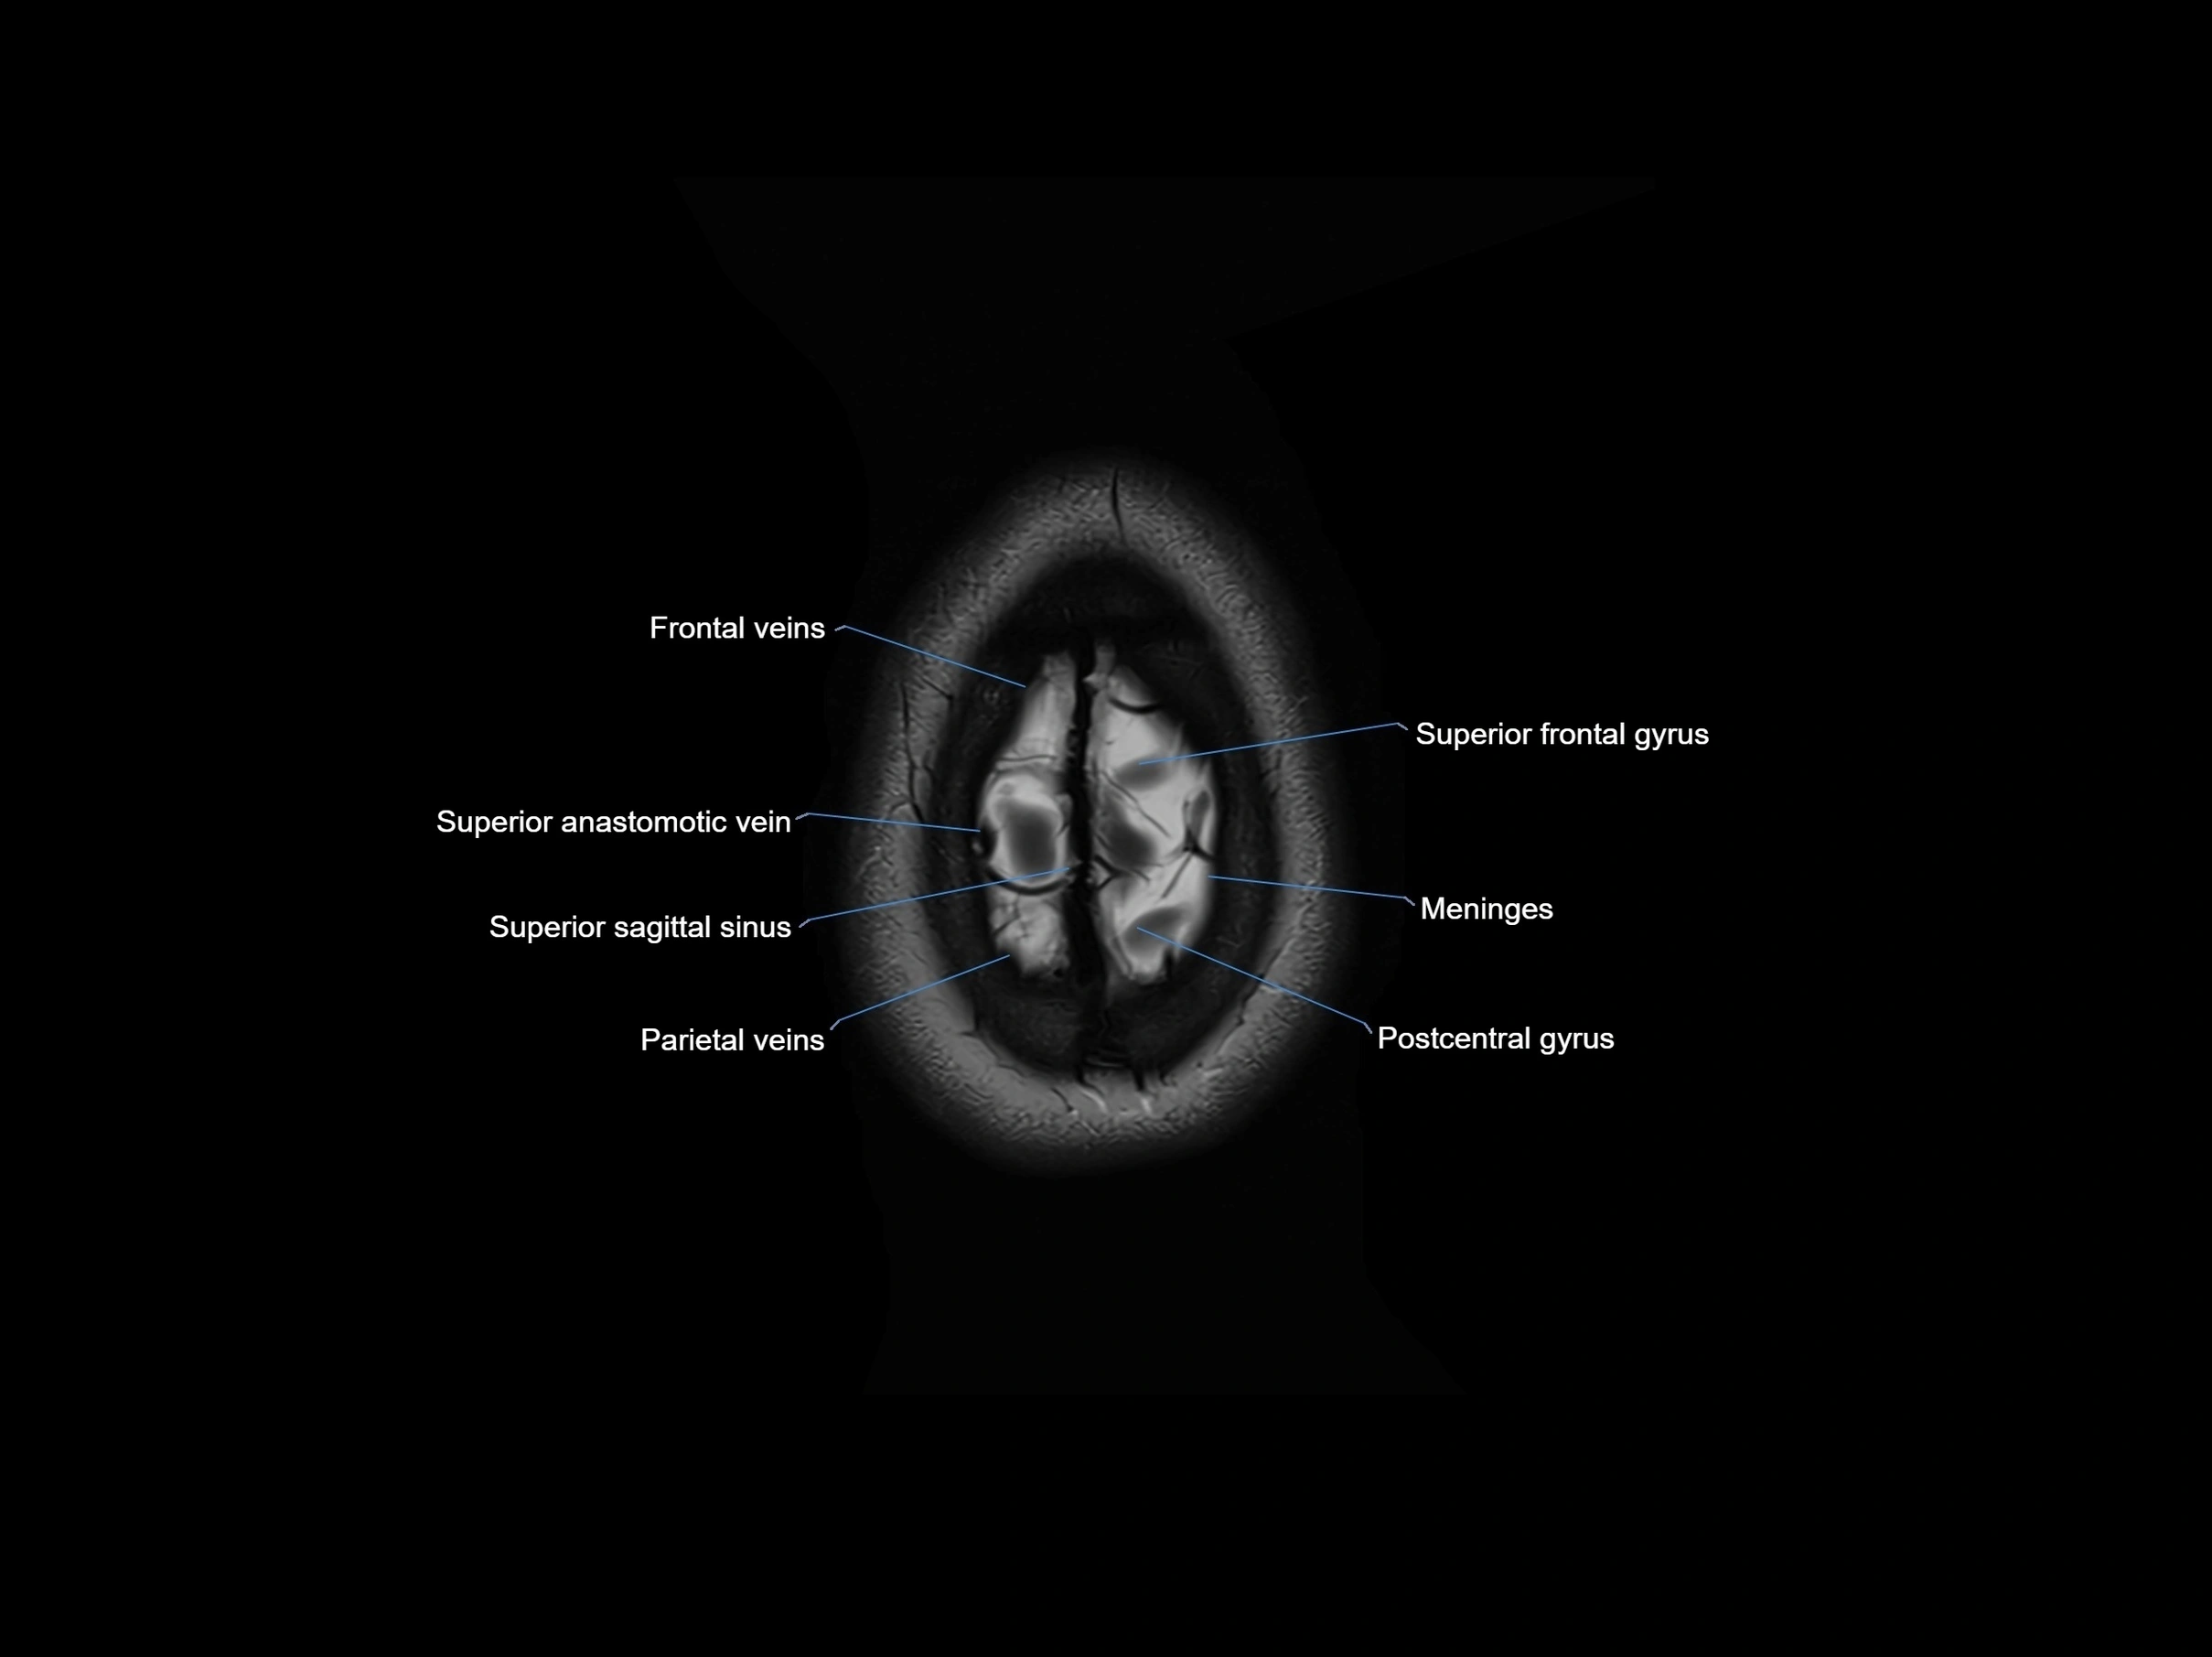

- Meninges

- Parietal veins

- Postcentral gyrus

- Superior anastomotic vein

- Superior frontal gyrus

- Superior sagittal sinus